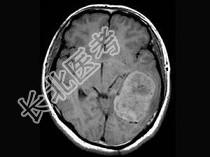

单项选择题女,34岁, 头痛数年,头颅MRI平扫及增强扫描, 最可能的诊断是 ( )

A、天幕脑膜瘤

B、星形细胞瘤

C、生殖细胞瘤

D、动脉瘤

E、三叉神经瘤